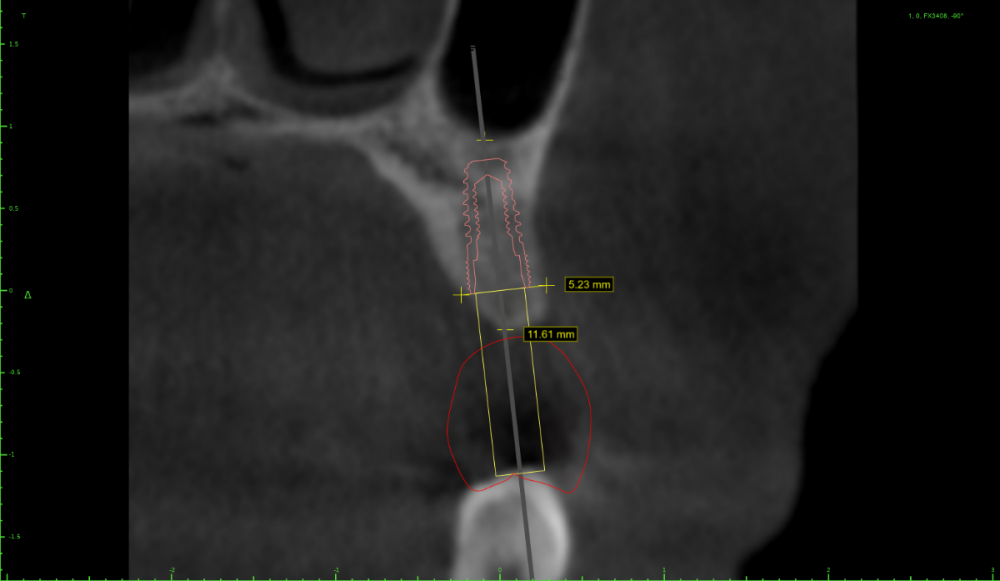

Irouil Опубликовано 4 мая, 2021 Поделиться Опубликовано 4 мая, 2021 (изменено) Тут стучать вообще не обязательно, просто пилотным сверлиться и экспандером расшириться. Если исходит из этого положения винта а если пойти ортодоксальнее и сместить его дистальнее, то ничего там при стуке не отломается Изменено 4 мая, 2021 пользователем Irouil Ссылка на комментарий

АнтонТЛТ Опубликовано 4 мая, 2021 Поделиться Опубликовано 4 мая, 2021 4.0*7.3 синус не нужен, нужна нкр Ссылка на комментарий

Irouil Опубликовано 4 мая, 2021 Поделиться Опубликовано 4 мая, 2021 (изменено) Не очень понял, что не так в предложенном автором вопроса варианте расстановки и зачем переходить на вариант с НКР и винтом 4.0? Изменено 4 мая, 2021 пользователем Irouil Ссылка на комментарий

АнтонТЛТ Опубликовано 4 мая, 2021 Поделиться Опубликовано 4 мая, 2021 Винт 4.0 потому что в данной системе, которую я поставил он 7.3мм, диаметром 3.5 только 8.5мм и более. У автора 3.6 на 7мм как я понял) Автор установил имплантат очень глубоко, чтобы избежать нкр и близко к клыка. Какой будет профиль прорезывания и что будет с костным пиком через несколько месяцев после протезирования? Ссылка на комментарий

Irouil Опубликовано 4 мая, 2021 Поделиться Опубликовано 4 мая, 2021 У меня нет дома просмотрщика с модельками, поэтому скриншотов не будет, но в целом соглашусь - нужно НКР. И вертикальный синус) Правда НКР несложная, дефект практически трехстеночный. На уровне платформы больше 3.5 мм не вижу ширину гребня Ссылка на комментарий

Женька Опубликовано 5 мая, 2021 Поделиться Опубликовано 5 мая, 2021 @АнтонТЛТ неа, 3.5*8 Можно конечно вариант который я ранее предлагал 7мм винт из которых 1.5мм полированная шейка. Но с НКР её(шейку) не совместить я так понимаю. Ссылка на комментарий